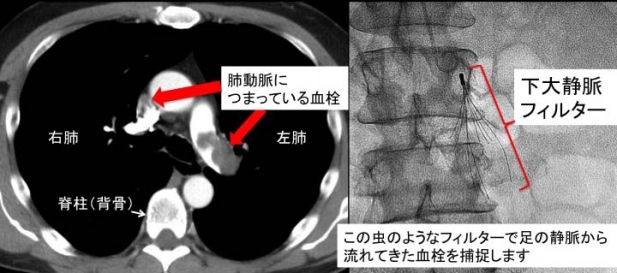

40代の患者さんが、不整脈のため紹介されてきました。2ヶ月前に左アキレス腱を断裂し、まだ松葉杖の状況でした。前日の午後職場で突然動悸息切れを自覚。数時間医務室で休んだ後かかりつけ医を受診したところ、心拍数が1分間130と速いため、脈を落ち着かせる薬を処方されました。当院受診時も心拍数は118/分と速く、何らかの頻拍発作(脈が速くなるタイプの不整脈)が続いていると考え心電図を分析しました。しかし、特殊な不整脈ではなく単に走った後のように脈が速い状態でした。最も考えられる病態は貧血(出血などで血液が足りない状態)ですが、そうではありませんでした。確定診断がついたのは心エコーという超音波診断装置を胸に当てた瞬間でした。“肺動脈血栓塞栓症”だったのです。一般には“エコノミークラス症候群”と言った方が分かりやすいかもしれません。先入観なしに考えるとすべてに納得がいきます。患者さんは2ヶ月前にアキレス腱の手術を行い、しばらくの間左足をギプスで固定され診察時も左足にはかなりのむくみがありました。足を動かせなかったため、下腿の静脈に血栓ができ、何かの拍子にそれが肺に飛んでいったと考えられました。肺における酸素取り込みが悪くなり、低酸素状態に反応して脈が速くなったのです。この患者さんは直ちに榊原記念病院に入院となりました。CTスキャンで肺動脈内に大量の血栓が証明され、血栓がこれ以上肺に飛んでしまうと生命に危険がおよぶため、血管内に下大静脈フィルターという器具(図示した虫のような形をしたものです)が留置されました。同時に血栓を溶かす薬が投与され病状は次第に改善しました。

数週間後の木曜日、榊原記念病院に行き、この患者さんに留置されていた下大静脈のフィルターを自分の手で体外に取り出しました。血管内異物回収テクニックです。カテーテル治療専門医は血管内に存在するX線透視で見えるものは、その場所にかかわらずほとんどすべて回収できる技術を備えています。実際のところはゲームセンターにあるUFOキャッチャーに似ているかもしれません。